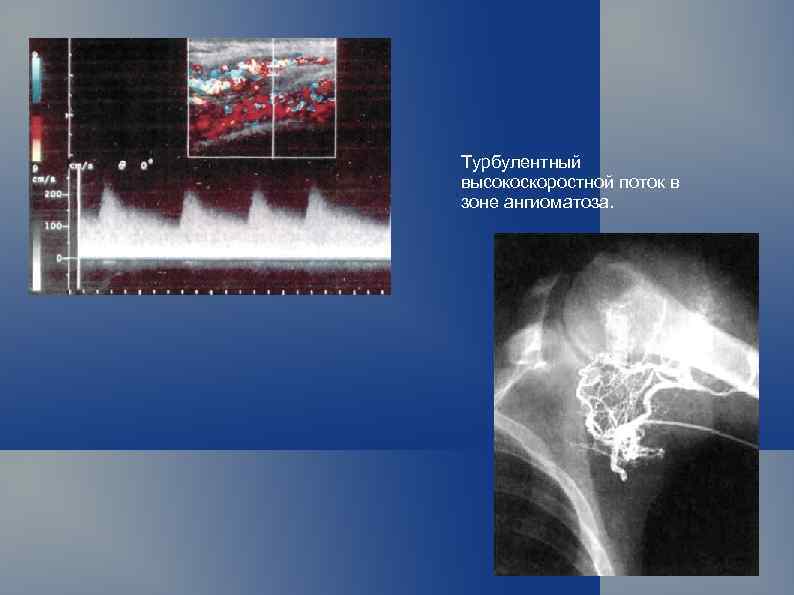

Турбулентный высокоскоростной поток в зоне ангиоматоза.